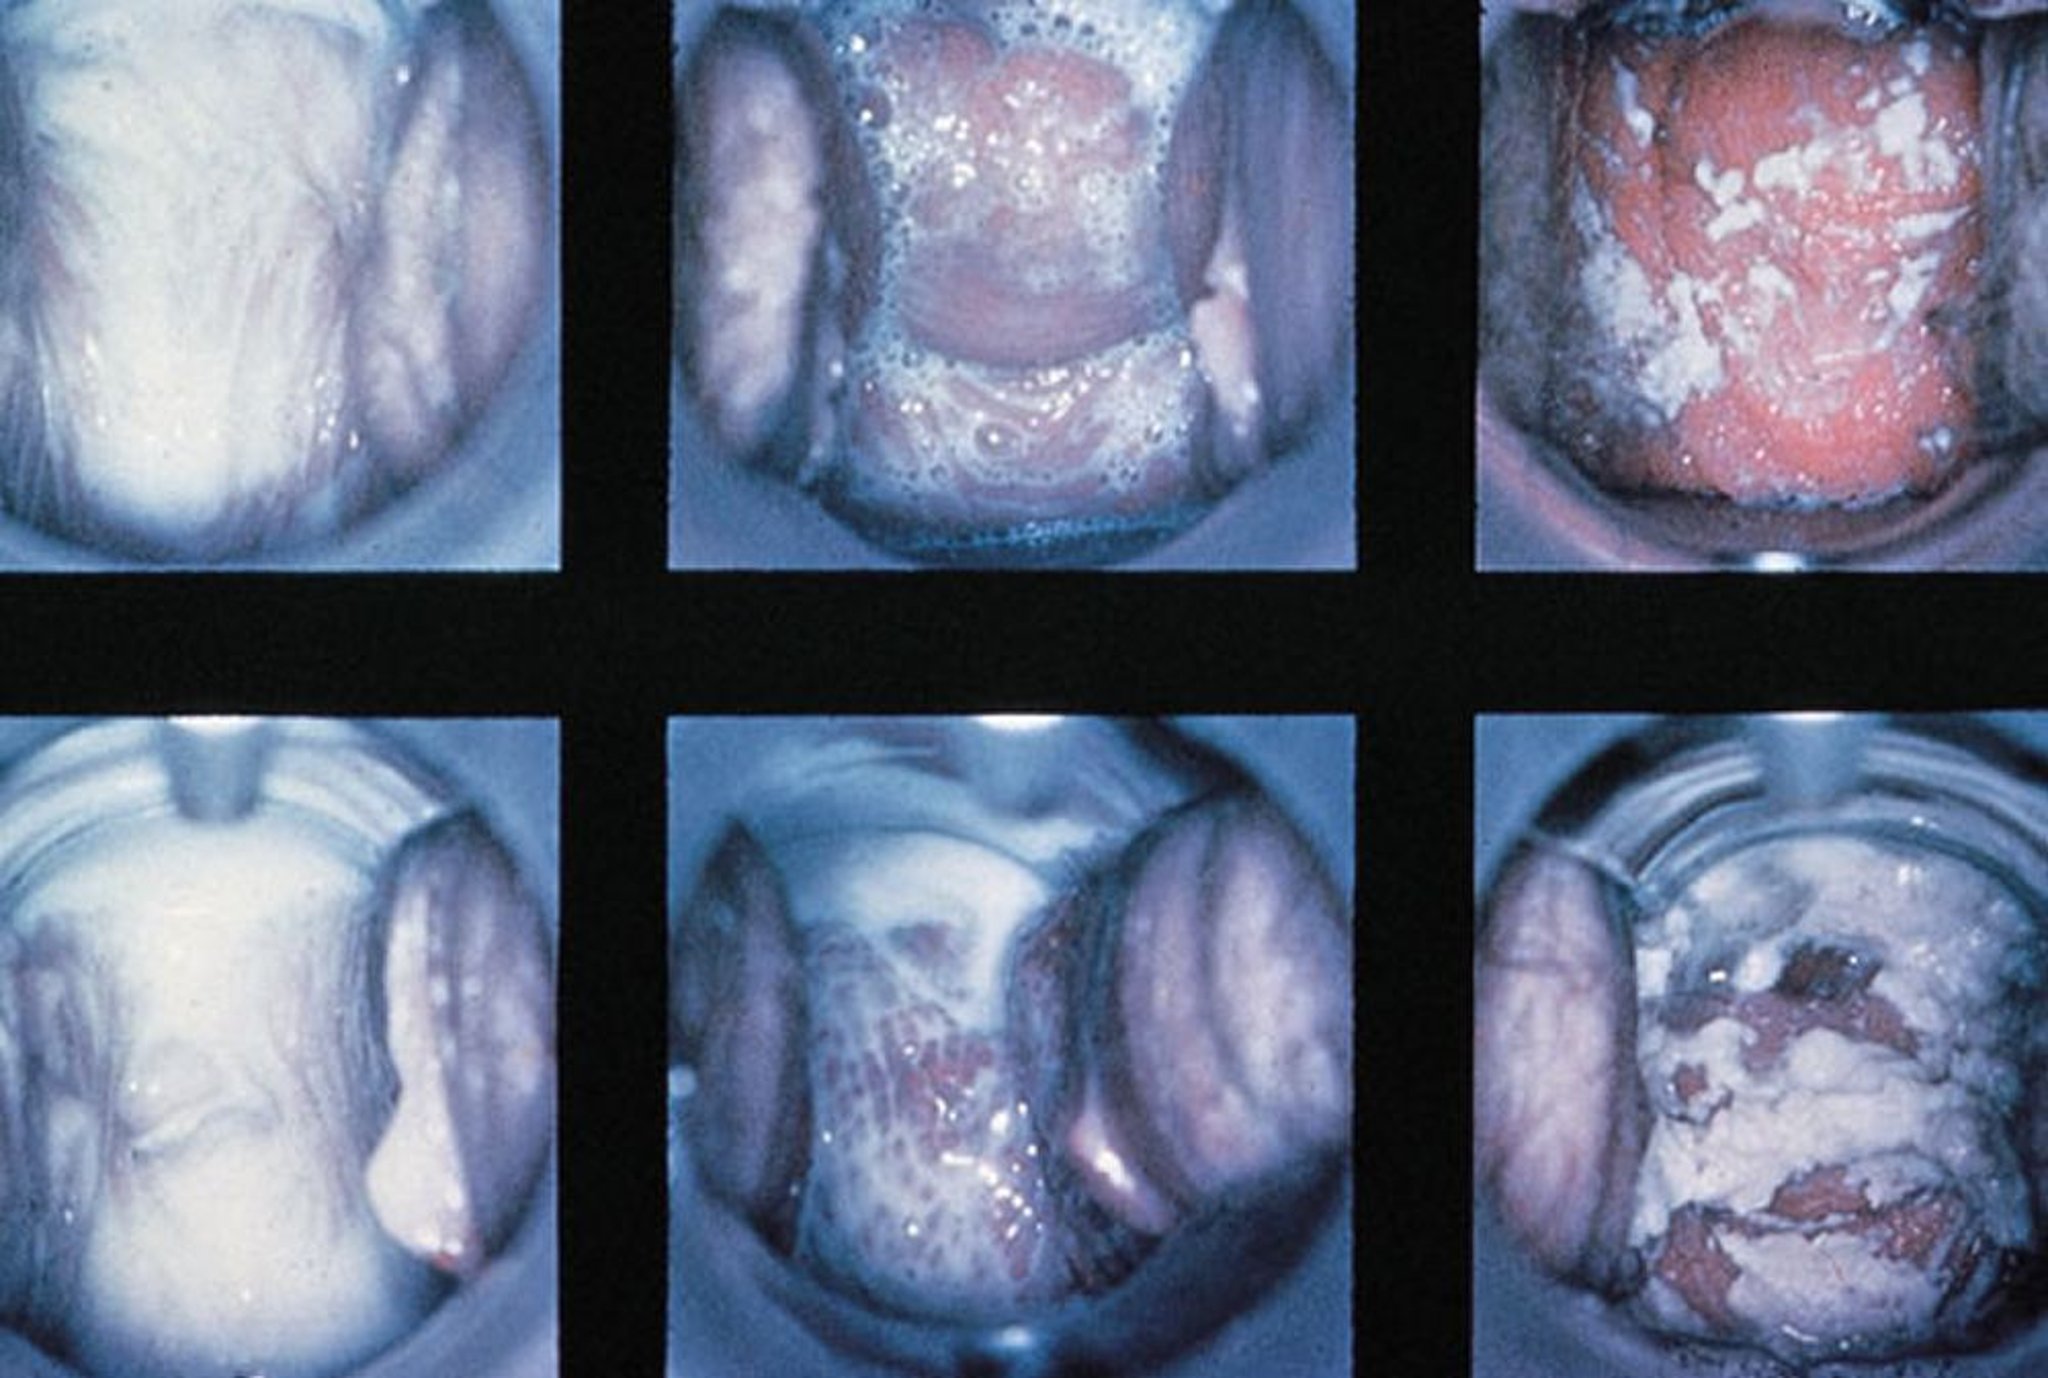

Khám mỏ vịt trong viêm âm đạo

Kết quả bình thường, viêm âm đạo trichomonal với dịch tiết bọt, và viêm âm đạo do nấm với dịch tiết đặc, trắng được hiển thị (trái sang phải).

Được sự cho phép của nhà xuất bản. Theo Spitzer M, Mann M. Trong Tập ảnh về Phụ khoa lâm sàng: Bệnh học phụ khoa. Biên tập bởi M Stenchever (biên tập loạt bài) và B Goff. Philadelphia, Current Medicine, 1998. (Được phép của Hiệp hội Quốc tế về Nghiên cứu bệnh âm hộ, từ bộ sưu tập của Dr. Herman Gardner.)